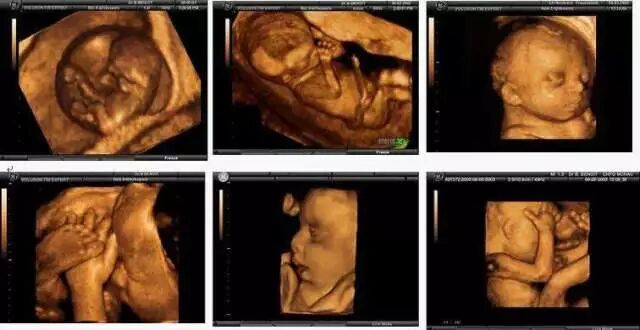

何为5D彩超?一堆专业术语帮主就不说了,简单些讲就是三星集团在二维、三维、四维超声的基础之上,研发出来的国际领先的彩超设备,5D彩超影像比四维彩超清晰度更高,诊断范围更全面,能够多方位、多角度地观察宫内胎儿的生长发育情况,为早期诊断胎儿先天性体表畸形和先天性心脏疾病提供准确的科学依据。

给你最直观的感受就是,成像效果超精细逼真!宝宝的彩超图像丰盈可爱,连他们细小的手指脚趾都能看清楚!

当然,这么高端的技术还是为了一件事:宝宝的健康!!!5D技术具有超高灵敏度的血流成像技术,能够检测到极其细小的末梢血管。新型的广角腔内探头,提供高达210度的扫查视野,方便腔内扫描。强大的数据处理和降噪能力,大大提高诊断的准确性。三维仿真成像速度更快,现实直观的诊断,也更方便医患及时沟通。

相较于之前的彩超技术,5D彩超除了基础排查胎儿的四肢是否发育健全(有木有缺少指头或是生殖器异形),更可筛查出包括无脑儿、开放性脊柱裂、致死性软骨发育不全、脑膨出、胸腹壁缺失的内脏外翻及单腔心的六大畸形和致死性胎儿畸形。所需要筛查的各项胎儿健康指标都能给出更精准的结果!

它的动态立体成像更直观更清晰,可对胎儿体表进行检查,同时对孕妇潜藏的各类疾病进行精确检测观察范围更广;能够多方位、多角度观察宫内胎儿生长发育情况,为早期诊断胎儿先天性体表畸形等疾病提供准确的科学依据。

在宝宝还未出生之前,通过先进的5D设备就能清晰的看到Ta的一切,并且记录下来,这些曾经只存在于幻想的画面,各种淘气的手舞足蹈,生动有趣的表情,打哈欠伸懒腰揉眼睛……它的珍贵对于爸爸妈妈来说,是任何昂贵的礼物都无法代替的。

最适合拍彩超的时间是怀孕中期22周至28周(最佳时间段是24至26周,这个时间段宝宝在子宫里还不算拥挤,面部轮廓清晰,更容易让宝妈宝爸先睹为快,看看长得更像谁!另外,三维彩超是图片,四维彩超是录像,而5D是图片录像都兼顾哦~